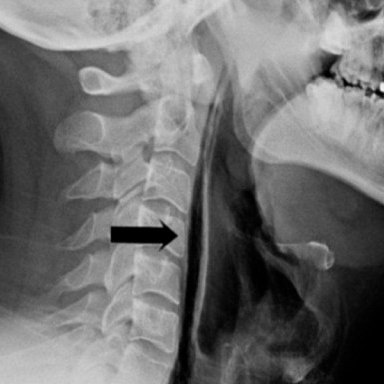

Мужчина попытался сдержать чих, зажав нос пальцами.

• После чиха он почувствовал резкие толчки в шее и заметил, что она начала опухать.

Врачи диагностировали разрыв пищевода.